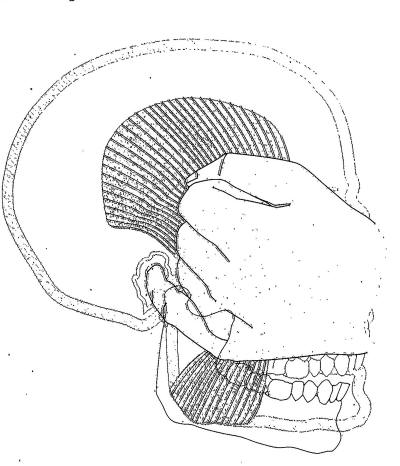

Palpación del músculo temporal |

El temporal también no presenta inconvenientes a la

palpación, dado que es un músculo menos poderoso que el

masetero, solemos pedirle al paciente que apriete sus

dientes co intervalos de descanso, para obtener respuesta

dolorosa a la palpación. |